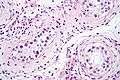

| Intratubular germ cell neoplasia. H&E stain. | |

ITGCN is not palpable, and not visible on macroscopic examination of testicular tissue. Microscopic examination of affected testicular tissue most commonly shows germ cells with enlarged hyperchromatic nuclei with prominent nucleoli and clear cytoplasm. These cells are typically arranged along the basement membrane of the tubule, and mitotic figures are frequently seen. The sertoli cells are pushed toward the lumen by the neoplastic germ cells, and spermatogenesis is almost always absent in the affected tubules. Pagetoid spread of ITCGN into the rete testis is common. Immunostaining with placental alkaline phosphatase (PLAP) highlights ITGCNU cell membranes in 95 percent of cases. OCT3/4 is a sensitive and specific nuclear stain of ITGCNU.[3]

ITGCN. H&E stain.